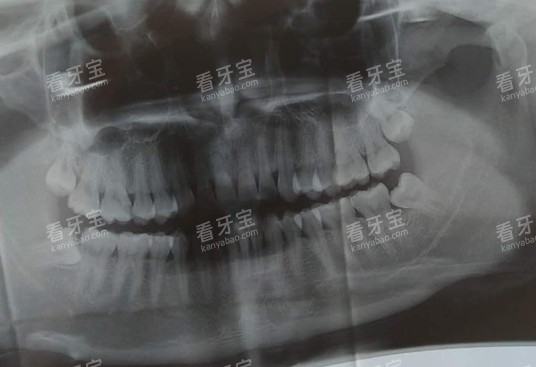

项目名称参考价格(元)说明普通挂号费5 - 10初诊/复诊口腔全景片80 - 120全口牙齿影像智能化根尖片30 - 50单颗牙影像超声波洁牙150 - 300含抛光喷砂洁牙200 - 400去除烟渍茶渍

?设备较高:配备德国卡瓦种植机、芬兰普兰梅卡全景X光机、瑞士EMS洁牙机等国内外主流设备。